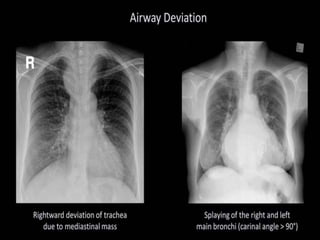

This document provides an overview of interpreting chest x-rays and identifies several key factors. It discusses the importance of inspiration, penetration, and rotation in obtaining a technically quality radiograph. It also outlines different views of chest x-rays including PA, AP, and lateral views. Finally, it identifies several anatomical structures that should be evaluated when interpreting a chest x-ray such as the lungs, heart, diaphragm, bones, and soft tissues.